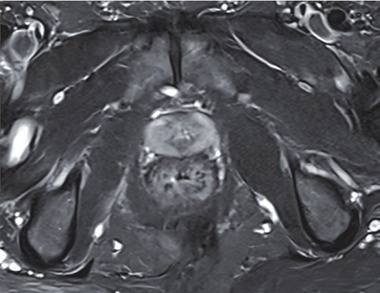

Abb. 1 MRT Beckenebene © Sven Schellberg

Wir berichten hier in diesem Kontext den Fall eines 54-jährigen Patienten, MSM, PLWH der sich extern mit lumbalen Schmerzen sowie mit beginnenden neurologischen Ausfallserscheinungen im Bereich beider Beine vorstellte. In der extern durchgeführten Magnetresonanztomographie bestätigte sich der Verdacht eines lumbalen Diskusprolaps, der neurochirurgisch versorgt werden musste.

Das MRT ergab jedoch den folgenden, auffälligen Nebenbefund: „Das Rektum imponiert wandverdickt, vermehrte Flüssigkeitseinlagerungen im präsakralen Fettgewebe ohne Nachweis einer abgekapselten Flüssigkeitsformation.“ (Abb. 1)

Radiologisch wurde dies interpretiert als „Wandverdicktes Rektum mit Imbibierungen des angrenzenden Fettgewebes DD entzündlich“, weshalb die Vorstellung bei uns zum Ausschluss einer rektalen Infektion erfolgte.